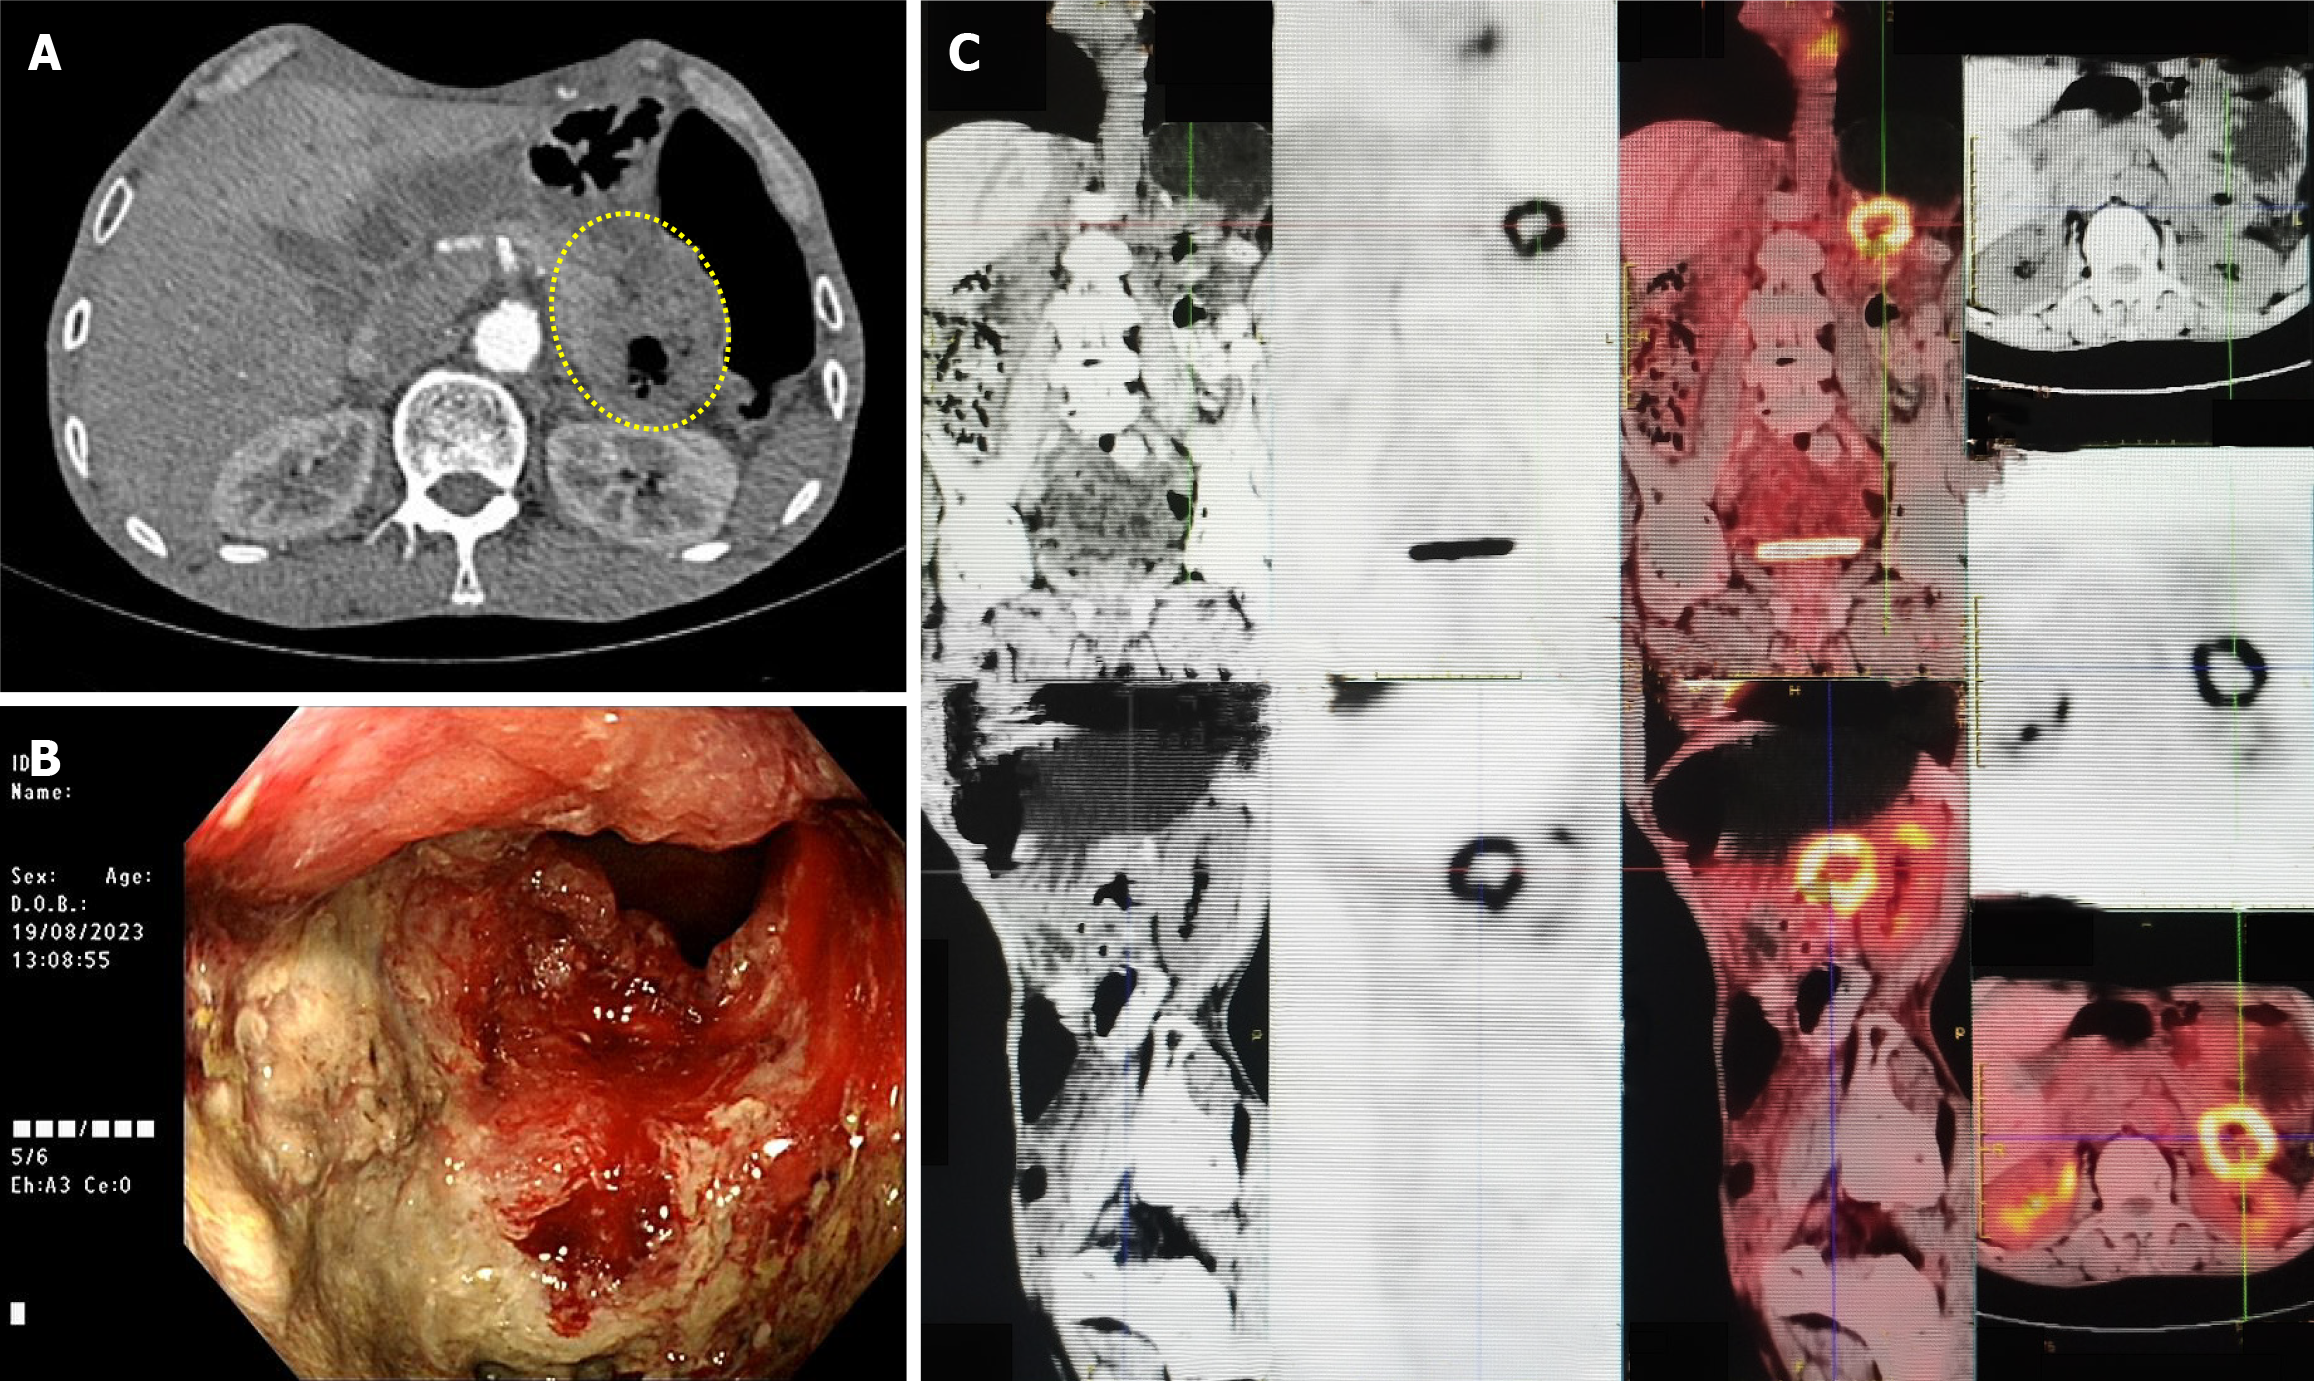

On contrast-enhanced computed tomography (August 19, 2023), descending colon wall thickening was observed (Figure 1A). On colonoscopy (August 19, 2023), an ulcerative, circumferential mass near the splenic flexure was identified (Figure 1B). On positron emission tomography-computed tomography (August 23, 2023), a hypermetabolic lesion with a maximum standardized uptake value of 10.0 was observed (Figure 1C).